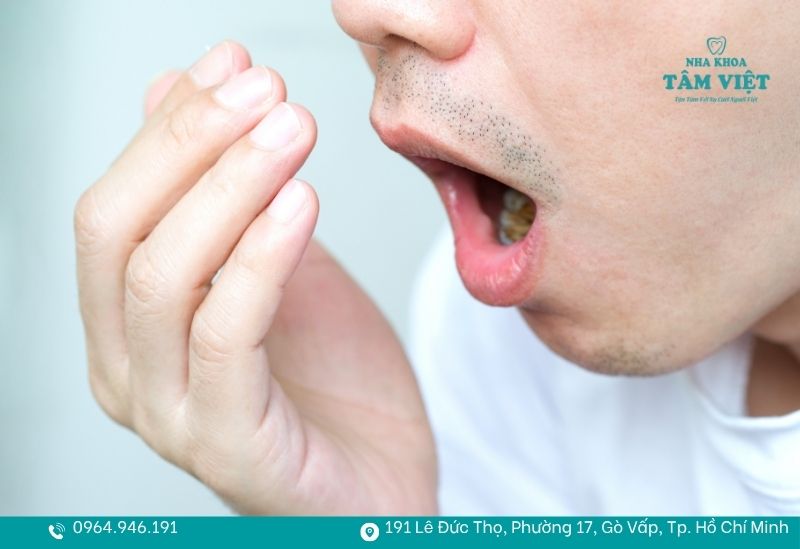

Hơi thở có mùi hôi nồng nặc và dai dẳng

Dù bạn đã đánh răng kỹ lưỡng hay sử dụng nước súc miệng thường xuyên nhưng mùi hôi vẫn không thuyên giảm? Đây là biểu hiện đặc trưng của viêm nha chu. Nguyên nhân là do các mảng bám vôi răng tích tụ lâu ngày tạo thành những túi nha chu sâu giữa răng và nướu. Đây là nơi cư trú lý tưởng cho vi khuẩn kỵ khí phân hủy protein trong thức ăn, giải phóng các hợp chất lưu huỳnh gây mùi hôi nồng nặc, khó chịu.